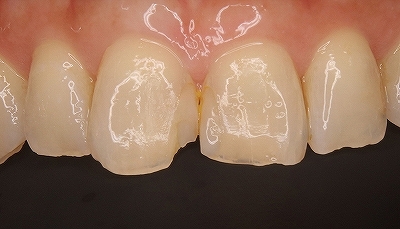

2025 EEdental YAH (2).jpg

この後仮歯を入れ経過観察